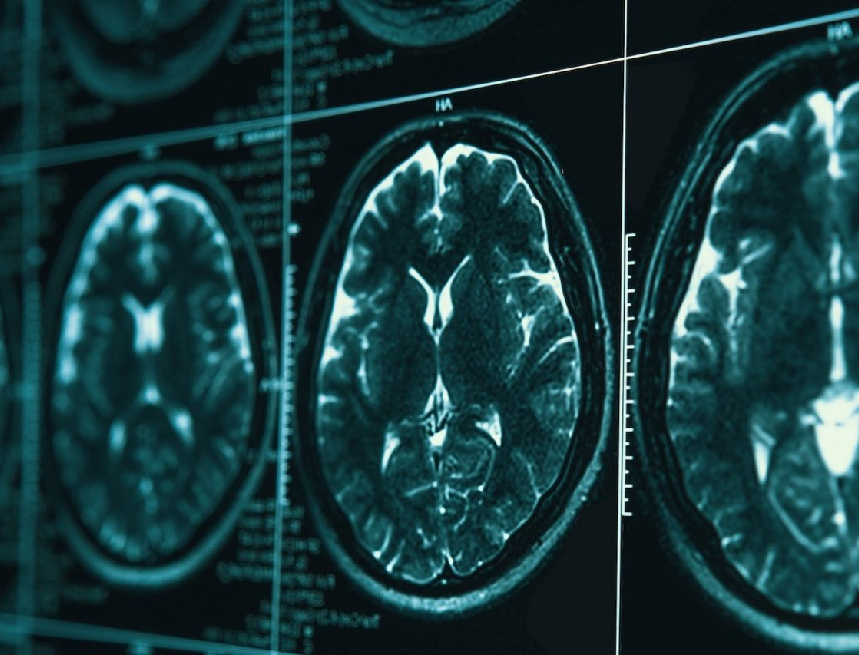

Μια νέα μελέτη από το Περού, δημοσιευμένη στο περιοδικό Frontiers in Neurology, εξετάζει τη σχέση ανάμεσα στην ασύρματη ακτινοβολία Wi-Fi και τη νόσο Alzheimer.

Οι ερευνητές εστίασαν σε γονίδια όπως τα GSK3B και APOE, που εμπλέκονται στην παθογένεση της νόσου, και διερεύνησαν την επίδρασή τους από ηλεκτρομαγνητικά πεδία συχνότητας 2,4 GHz – αντίστοιχης με αυτή των οικιακών δικτύων Wi-Fi. Η μελέτη έδειξε ότι η έκθεση σε 2,4 GHz μπορεί να διαταράξει τη γενετική ρύθμιση που αφορά το οξειδωτικό στρες και την πρωτεϊνική ισορροπία, προκαλώντας μετουσίωση πρωτεϊνών και σχηματισμό πρωτεϊνικών συσσωματωμάτων, χαρακτηριστικών της νόσου Alzheimer. Οι συγγραφείς δεν αποδεικνύουν αιτιώδη σχέση, αλλά επισημαίνουν ότι τα ευρήματα αυτά υποδεικνύουν μια λεπτή βιολογική ευπάθεια του εγκεφάλου απέναντι στη συνεχή ηλεκτρομαγνητική επιβάρυνση.